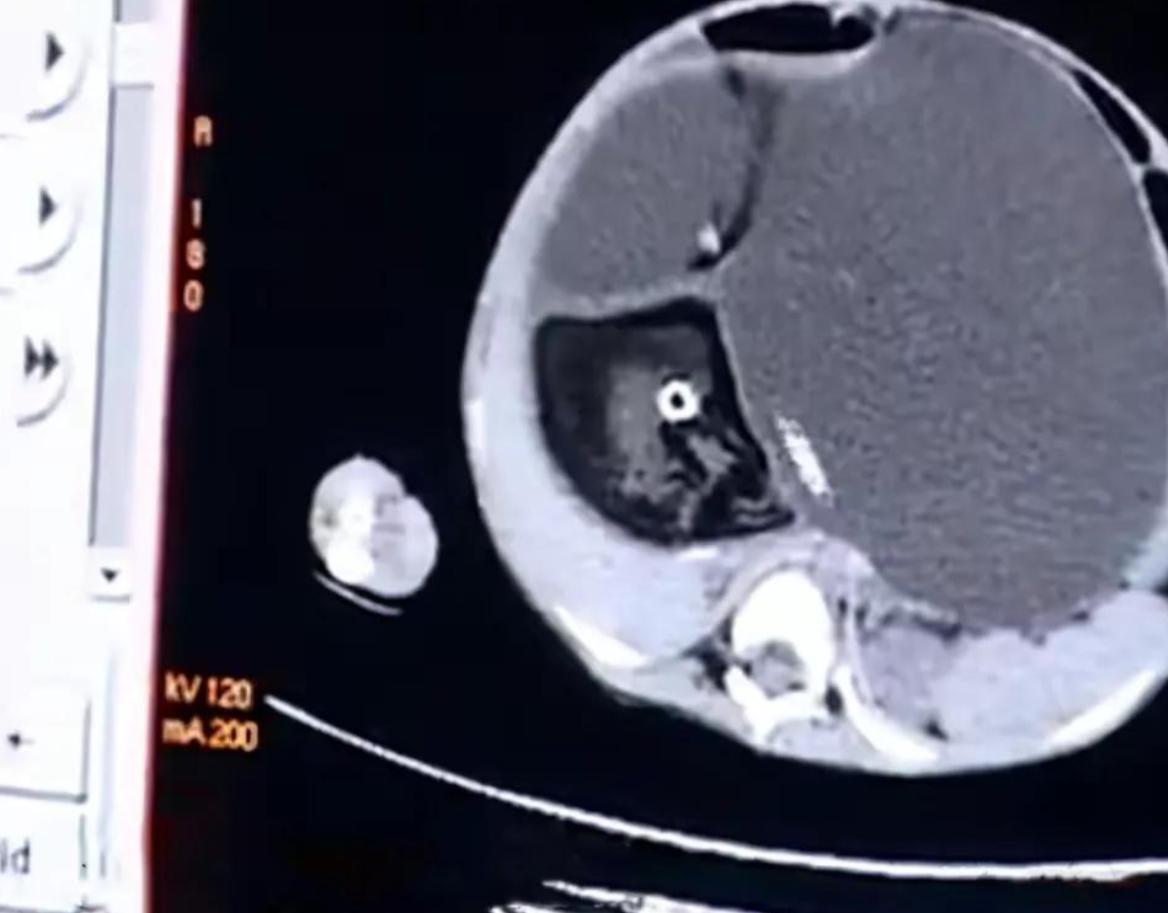

到了市裏面的醫院就有CT了,在進行CT檢查的時候醫生就發現了康夢茹的病因,原來她肚子裏面有一個胎兒,還能看得清楚的毛髮和牙齒,但是這個胎兒其實已經死了。

雖然這個胎兒不是活的胎兒,但是包裹着胎兒的部分就會在不斷的變大,這樣的情況也叫做先天性畸胎瘤。

醫生說之前看過了先天性畸胎瘤也有,但是這麼大的還真的沒有看到過,這麼大的會壓迫他的肺部,還壓迫他的神經,對於他的血管神經都會有影響,所以這樣的手術難度還是比較高的。